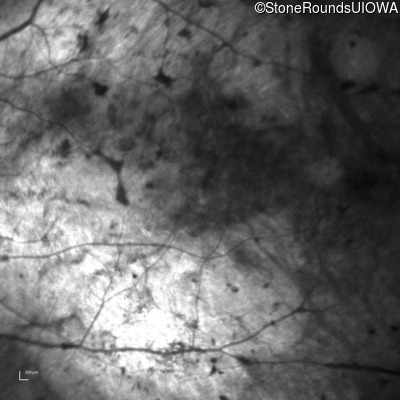

Infrared Fundus Photograph - Right - Light Perception

Exemplar